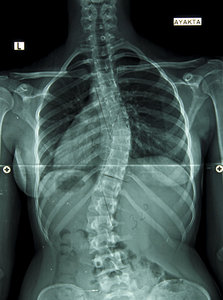

Scoliosis is a lateral curvature of the spine that measures 10 degrees or more. An idiopathic scoliosis is accompanied by vertebral rotation and rib-cage deformity, and usually becomes progressively apparent as the spine grows during childhood.